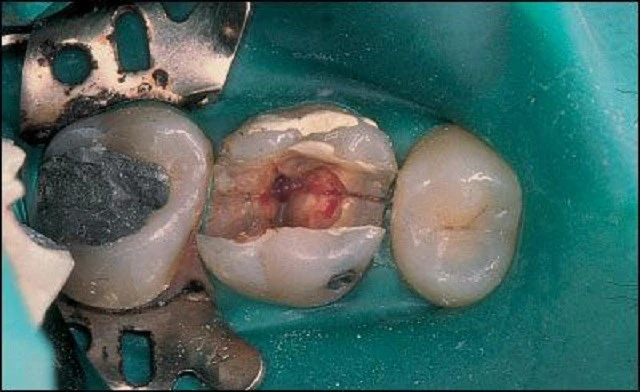

Tìm vết nứt

Nứt dọc chân răng đôi lúc có thể quan sát được trên lâm sàng. Sử dụng kính hiển vi phẫu thuật là rất hiệu quả khi thăm dò vết nứt, gãy trên bề mặt thân – chân răng. Dò tìm vết nứt có thể gây đau, thậm chí là làm mảnh răng lung lay, điều này gợi ý chia chân răng. Để xác định độ lan rộng của vết nứt, đặt áp lực lên các múi răng gần bất kỳ vết nứt nào.

Kính hiển vi nha khoa

Kính hiển vi được dùng trong lĩnh vực y học trong nhiều năm qua, kính hiển vi nha khoa là một công cụ vô giá trong quá trình điều trị nội nha. Với khả năng phóng đại lên đến 25 lần, ánh sáng tuyệt vời, bác sĩ có thể quan sát những chi tiết trong thân răng và ngoài thân răng với độ chính xác cao. Đôi lúc một vết nứt có thể được nhìn thấy bên ngoài răng trước khi điều trị nội nha, sau khi mở xoang tuỷ độ sâu của nó cũng có thể quan sát được trong thân răng bằng kính hiển vi nha khoa.

Phương pháp chiếu sáng và dùng thuốc nhuộm

Đôi khi cần phải tháo miếng trám trên răng để có thể quan sát vết nứt rõ hơn. Nhuộm bằng Xanh Methylene bằng cách bôi thuốc lên bề mặt răng bằng đầu tăm bông, thuốc nhuộm sẽ quyên qua vùng nứt và xác định vị trí đường nứt. Chiếu sáng cũng có thể hữu ích hơn bằng cách chiếu trực tiếp ánh sáng có cường độ cao vào bề mặt răng tại đường nối men – xi măng để xem mức độ lan rộng của vết nứt. Phần răng gần với nguồn sáng sẽ hấp thu ánh sáng và phát sáng, trong khi phần răng phía bên kia của vết nứt không được sánh sáng truyền qua sẽ có màu xám hơn. Mặc dù có thể phát hiện được vết nứt bằng thuốc nhuộm hoặc ánh sáng nhưng độ sâu của vết nứt không thể lúc nào cũng xác định được.

– Tiên lượng trung bình: Nếu răng nhạy cảm khi thăm dò đường nứt mặt nhai, mảnh răng không di động, việc tiên lượng trở nên khó khăn hơn. Bệnh nhân cần hiểu được rằng điều trị nội nha có thể không giải quyết được các triệu chứng và tiên lượng cuộc điều trị chỉ ở mức khá thôi. Nếu thực hiện điều trị nội nha, cần kiểm tra các thành bên trong xoang tuỷ cẩn thận, tốt nhất là nên dùng kính hiển vi nội nha (DOM) có chiếu sáng để xác định xem đường nứt có lan rộng vào vùng buồng tuỷ và ống tuỷ không.